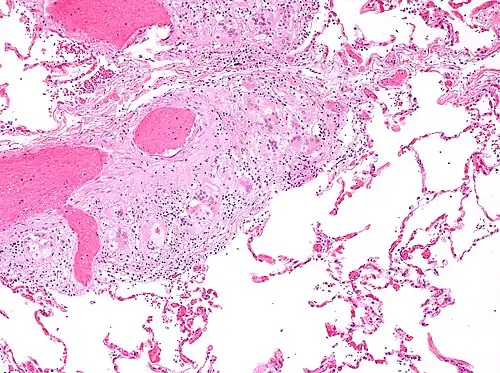

Histopathology

Sarcoidosis is characterized by the formation of non-necrotizing ("non-caseating") granulomas in various organs and tissues.[95] Giant cells, specifically Langhans giant cells, are often seen in sarcoidosis.[96] Schaumann bodies seen in sarcoidosis are calcium and protein inclusions inside of giant cells as part of a granuloma.[97] Asteroid bodies can be seen in sarcoidosis.[97] Hamazaki–Wesenberg bodies can be seen in lymph nodes and more rarely in lung biopsies with sarcoidosis and are inclusion bodies of lysosomes with protein, glycoprotein and iron.[98]

-

Sarcoidosis in a lymph node -

Schaumann body in sarcoidosis -

Asteroid body in sarcoidosis -

Hamazaki–Wesenberg bodies in sarcoidosis in lymph node